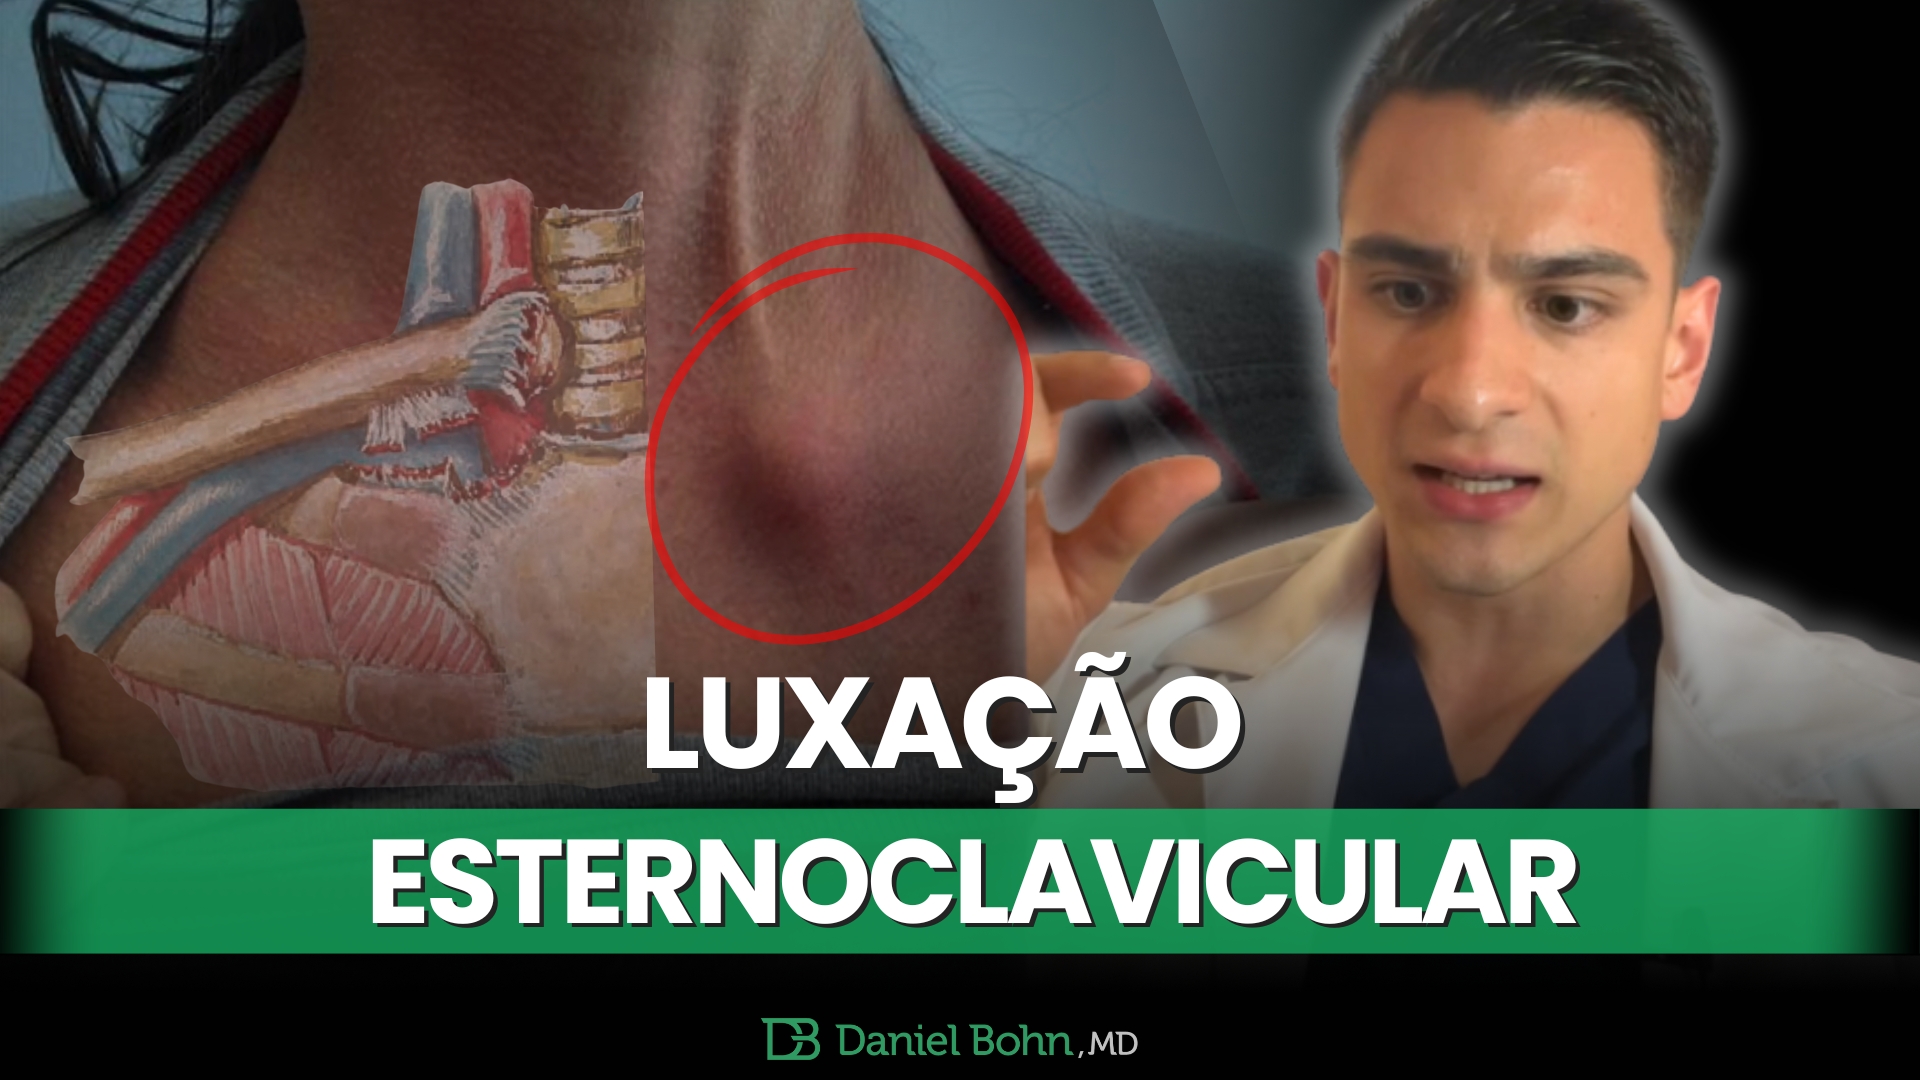

Guia Completo sobre Anatomia, Tipos e Tratamentos com Casos de Atletas A Luxação Esternoclavicular (LEC), embora incomum, representa uma lesão significativa …